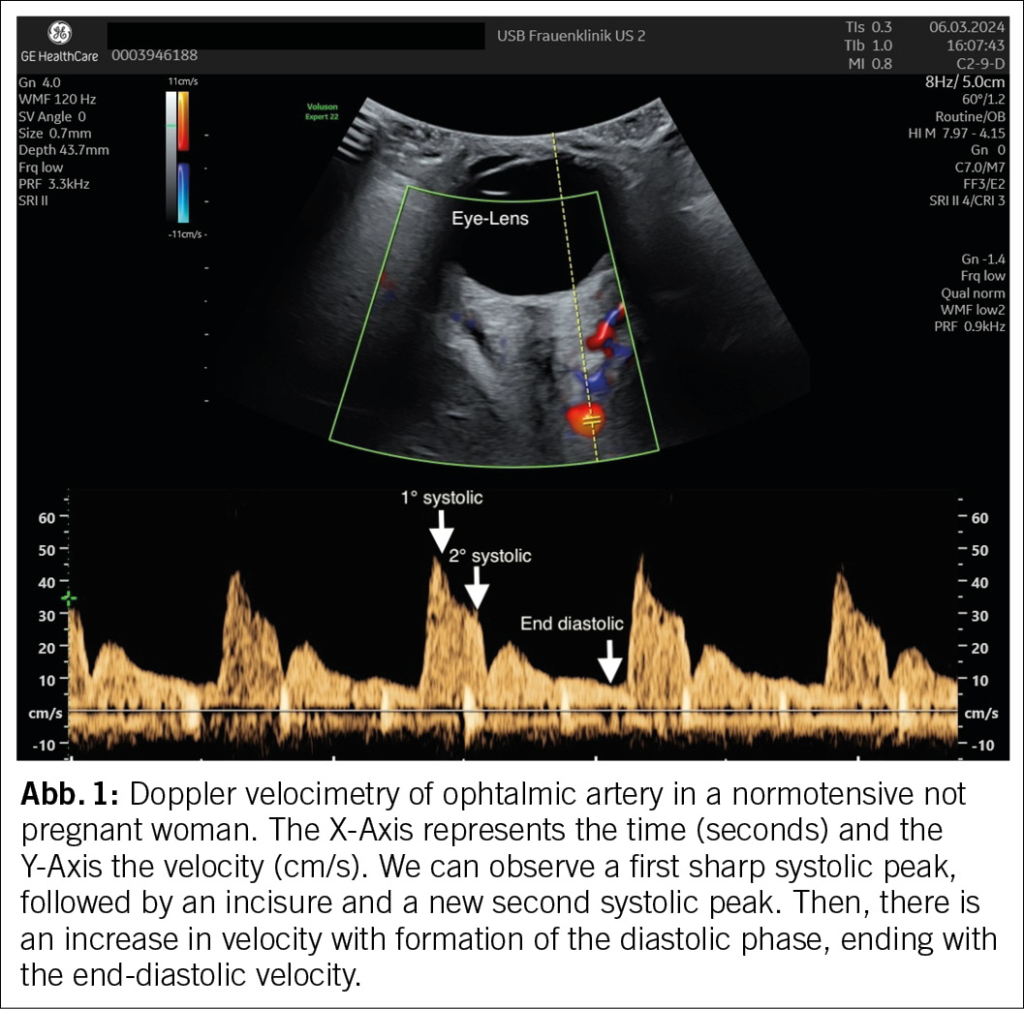

Die A. ophthalmica (Abbildung 1) wird am besten mit einer 7.5 MHz-Linearsonde gedopplert. Das Flussmuster weist zwei systolische Peaks auf. Im zweiten und dritten Trimenon zeigte sich, dass die Ratio dieser beiden PSV (peak systolic velocity, Maximalgeschwindigkeit) ein nützlicher PE-Marker ist (18;19). Kleinere Studien zeigten auch einen prädiktiven Wert in der alleinigen Messung der PSV des zweiten Peaks, dies konnte aber im grösseren Kollektiv nicht bestätigt werden (20). Der Doppler der A. ophthalmica wurde auch im ersten Trimenon untersucht und es wurde fest-gestellt, dass die PSV-Ratio beim Screening auf pPE ein guter prädiktiver Wert ist (21). Die Resultate sind noch von einem grösseren Kollektiv zu bestätigen (19). Während der direkte Zusammenhang zwischen einer gestörten Plazentaimplantation und einem erhöhten Widerstand in den A. uterinae einleuchtet, weist ein verändertes Flussmuster in der A. ophthalmica eher auf eine kardiovaskuläre Grundproblematik hin (22). Das glykosylierte Fibronectin (GlyFn) ist ein anderer vielversprechender Marker, der bei präeklamptischen Patientinnen erhöht ist (23;24). Eine Studie zeigte, dass die Vorhersagekraft für eine PE innerhalb von 2 Wochen nach der GlyFn-Untersuchung ähnlich hoch war wie die von PlGF und dem sFLT-1 / PlGF-Ratio, mit einer Entdeckungsrate von etwa 75 %, bei einer FPR von 42 % (25). Allerdings dürften weder GlyFn noch angiogene Faktoren die Behandlung von Frauen mit chronischem Bluthochdruck verbessern, da ihre Vorhersagekraft für eine überlagernde PE gering sind (25;26).